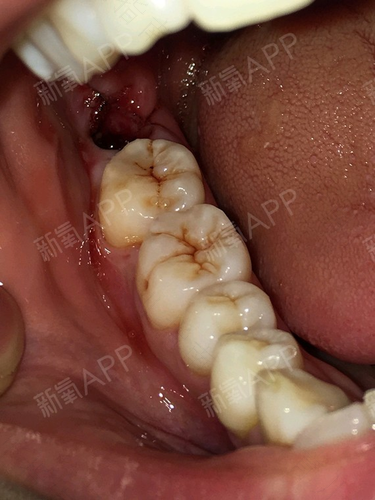

牙齿是人们重要的器官之一。世界上很多好吃的食物都要通过牙齿来咀嚼再送入胃里,如果没有牙齿,就会错过很多美食。但是牙齿也会生病,严重的话也要把它拔掉,那么拔完大牙后一般痛几天呢?

一般来说,拔完大牙后会疼痛两三天。因为拔完大牙后,还会有牙根留在里面,就会有疼痛感。倘若断根不是太大,一般疼痛两到三天就好了,但如果断根过大的话,就有可能造成持续的疼痛。如果疼痛感持续太久,那么建议去医院检查进行治疗。